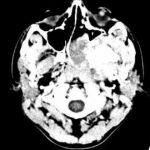

وبعد إجراء الاستقصاءات الشعاعية اللازمة بينت الدكتورة الجاسم أن صورة الطبقي المحوري مع الحقن أظهرت آفة غير متجانسة تملأ جوف الأنف الأيسر ممتدة للحفرة الجناحية الحنكية وصولاً للحفرة تحت الصدغية مع تورم بسيط للجيب الوتدي إضافة إلى ملاحظة تقوس الجدار الخلفي للجيب الفكي فيما بينت صورة المرنان المغناطيسي مع الحقن أن الآفة لا تغزو النسيج الدماغي وتم تصنيف الورم من النوع الثاني- الثالث.